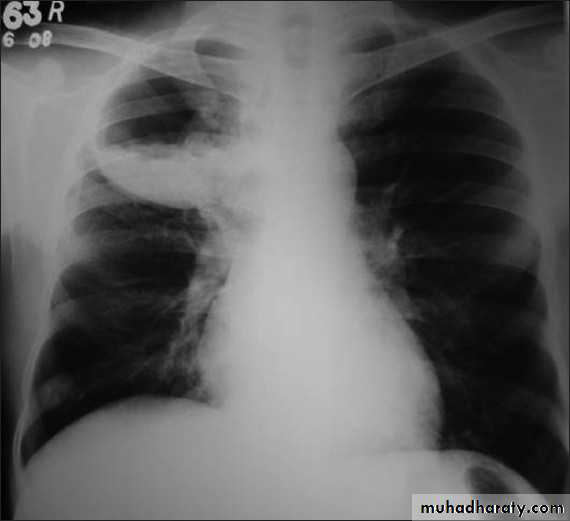

RT lower lobe collapse

usually the medial aspect of the dome of right hemidiaphragm is lost.the right hilum is depressed

It is important to note that the right heart border, which is contacted by the right middle lobe remains well seen.

Left lower lobe collapse has distinctive features, and can be readily identified on frontal chest radiographs, provided attention is paid to the normal cardiomediastinal contours. The shadow cast by the heart does however make it harder to see than the right lower lobe collapse

Radiographic features

Left lower lobe collapse

is readily identified in a well penetrated film of a patient with normal sized heart, but can be challenging in the typical patient with collapse, namely unwell patients, with portable (AP) often under-penetrated films, often with concomitant cardiomegaly. Features to be observed include :

triangular opacity in the posteromedial aspect of the left lung

edge of collapsed lung may create a 'double cardiac contour'

left hilum will be depressed

loss of the normal left hemidaphgragmatic outline

loss of the outline of the descending aorta

RT ULC

LT L L collapse

RT middle lobe collapse

RT L L collapse